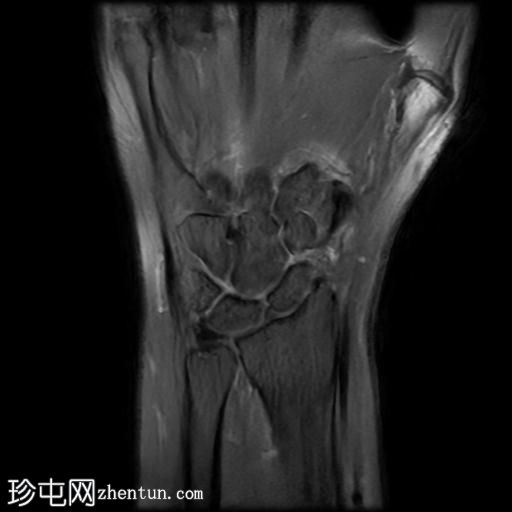

桡侧腕屈肌管综合征

持续性腕掌桡侧疼痛超过5个月。

MRI

轴位PD序列

脂肪抑制序列

桡侧腕屈肌腱鞘内可见液体信号,提示腱鞘炎

手部桡侧腕屈肌腱远端扁平,邻近的大多角骨嵴和舟骨结节可见反应性骨髓水肿

MRI结果提示存在桡侧腕屈肌腱病变,以及大多角骨和舟骨结节骨髓水肿。桡侧腕屈肌(FCR)肌腱病通常表现为腕关节掌侧(靠近桡侧)疼痛。这种情况通常是由于长期过度使用造成的,尤其是在肌腱与粗糙表面接触的部位。